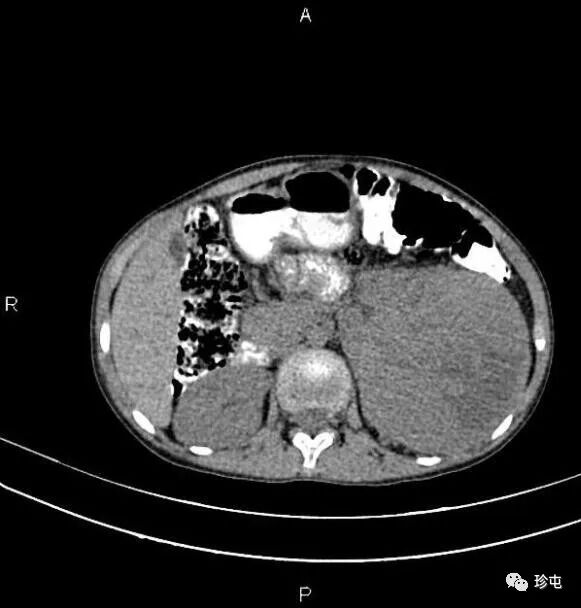

肾肿瘤的中医针灸治疗,28天左右就可以治好肾肿瘤约95%是恶性的,良性的很少见。恶性的肾肿瘤依据发病年龄和病理学的特点,可分为两大类型:①幼儿的肾肿瘤:多称为肾胚胎瘤,大多发生在3岁以前。②成人的肾肿瘤:常见于40岁以上。发生于肾实质的癌肿称为肾实质癌,发生于肾盂的癌肿称为肾盂癌。症状表现肿瘤累及肾盂时,可发生血尿。可以在还没有发生泌尿道症状前,已先有血行或淋巴道转移,肿瘤可累及淋巴或肺、肝、骨骼等。血尿、腹内肿块和腰部疼痛是本病的三个主要症状。在成人,血尿是比较早期和常见的症状。血尿多为肉眼可见的全血尿;也有的血尿只能在显微镜下才能见到。一般在血尿时病人不痛。血尿多是间歇性的。1.良性肿瘤注意有无血尿。2.肾癌(又称肾细胞癌、肾透明细胞癌)注意发病年龄及有无下述表现:①间歇性无痛性血尿、肾区钝痛,并可出现全身症状,包括低热、贫血、红细胞计数增多、高血压、高钙血症等。②肾区叩击痛,肾肿大,症状性精索静脉曲张及腹部肿物。3.肾盂癌发病年龄及有无下列症状表现:早期即出现肉眼血尿,肾绞痛及肾积水。②静脉尿路造影:显示肾盂不规则充盈缺损,肾盏、肾盂积水,输尿管种植癌。③尿内可查到癌细胞。4.肾母细胞瘤(胚胎瘤)发病年龄(大多发生在幼儿,偶见于中青年)及有无下述表现:①以腹部肿物为第一症状,贫血、低热、高血压常见,但血尿少见。②尿路造影不显影或显示肾盂、肾盏变形移位,肾影增大,肿瘤区可见钙化影,输尿管可被肿瘤推向中线。③放射性核素肾扫描,显示患肾放射性缺损及稀疏。④肺、骨骼可有早期转移。中医针灸治疗肾肿瘤效果较好,一般28天可以治好。

【“爱笑的女孩”婷婷不幸离世,年仅11岁,生前遗憾或是未能见妈妈一面】11月2日凌晨5时许,来自河南濮阳的抗癌博主“婷婷打怪兽”不幸离世,年仅11岁。3日,该账号的运营者赵女士告诉@极目新闻 记者,账号记录的是侄女婷婷的抗癌生活,希望她能被更多人记住,也希望肾母细胞瘤这个疾病被更多人知晓。#家人提前三个月为11岁抗癌女孩庆生#婷婷的病情始于2023年6月底,正在读三年级的她在学校出现腹痛症状。起初家人以为是普通肠胃不适,在村里诊所拿药后未见好转,随后辗转多个医院被确诊为肾母细胞瘤。“我们之前从没听过这个病,一点了解都没有,当时整个人都蒙了。”赵女士回忆道。确诊后仅四五天,婷婷接受了第一次手术,右肾被切除。术后家人本以为病情能得到控制,却没想到这只是抗争的开始。2023年11月,距离第一次手术仅半年,婷婷的病情复发,肿瘤转移至肝门及右肾手术末端,家人只能带她进行第二次手术,切除转移病灶。两次手术后,化疗、放疗成为婷婷生活的常态。2024年初,病情暂时稳定的婷婷曾重返校园两个月,彼时她已升至四年级。“她成绩特别好,之前在班里一直是前三名,半年没上学,晚上学到十一点也要把落下的课程补回来,考试还能考九十多分。”赵女士说。2025年3月,家人带婷婷到济南做全身检查,结果显示无复发迹象,婷婷重拾信心。“我们当时都以为她要好了。”赵女士说。然而,今年4月,婷婷在郑州复查时被查出肝门肿瘤复发,化疗后更出现严重骨髓抑制,险些丧命。8月底再次检查显示肿瘤扩散,医生表示已无治疗价值。“最后这段时间她就躺在家里,完全不想出门,肚子里长满了肿瘤,离开的时候肚子跟六个月的孕妇一样大。